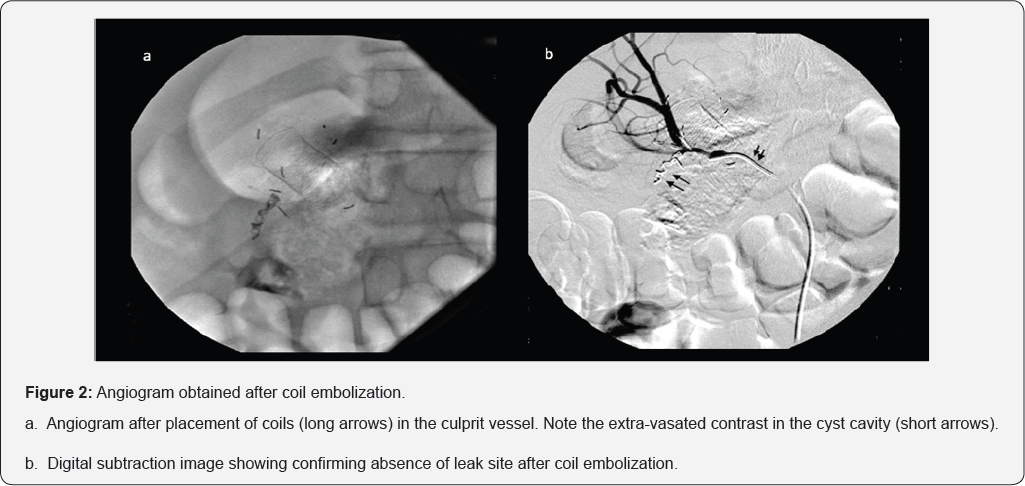

A 12-year old boy was hospitalized with history of acute necrotizing pancreatitis (7 weeks). Evaluation revealed large walled off necrosis (WON). The child had persistent symptoms in form of pain abdomen and intolerance to oral diet. Endoscopic ultrasound (EUS) guided drainage was performed using a lumen apposing metal stent (LAMS). The drainage procedure was accomplished without any immediate untoward consequences. There was significant improvement in clinical symptoms as well as the size of WON on day 3 of drainage. However, the child had a large bout of hematemesis on day 4 of drainage. Gastroscopy revealed LAMS in situ and partially occludedby a large clot arising from the cyst cavity (Figure 1a & 1b). Urgent angiography was performed via right femoral artery, which revealed leak from superior pancreaticoduodenal artery (Figure 1c &1d). The leak of contrast was localized along the lateral edge of LAMS, near farther end. Coil embolization was done following which there was no extravasation of contrast from the artery involved (Figure 2a & 2b).